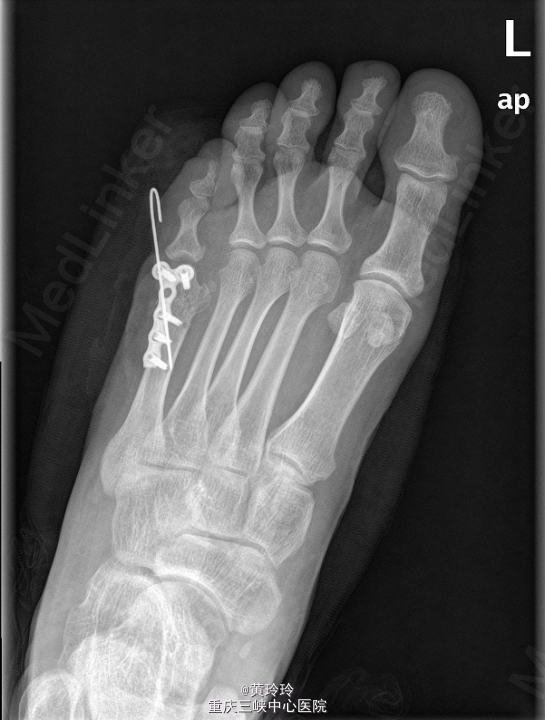

初步诊断:左足多趾畸形.在硬膜外麻醉下行左足多趾截趾加第五跖骨截骨矫形术. 取第5趾两侧切口,保留部分趾蹼皮肤,分离筋膜,去除第五趾。并予第五跖骨远端截骨,截去第五跖骨内侧部分跖骨头,将第六趾移向内侧,接近正常位置,克氏针斜行固定。C臂透视位置可,予T形锁定钢板及螺钉固定。

出院后下肢避免完全负重,避免剧烈活动。术后2周左右拆线。一月后拔除克氏针(具体待X拍片后决定).